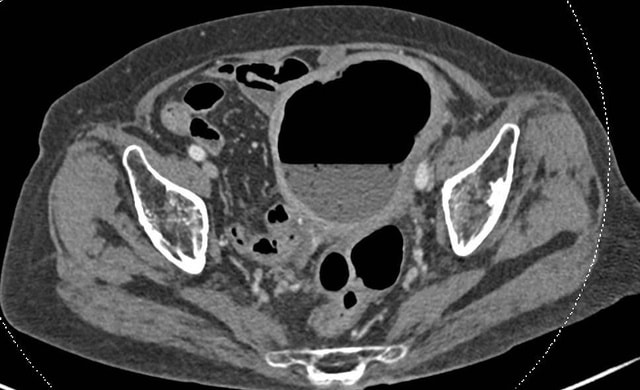

Cụ M.T.M. (88 tuổi, TP.HCM) được người nhà đưa đến Bệnh viện FV trong tình trạng sốt, đau bụng âm ỉ không dứt, âm đạo tiết dịch mủ. ThS.BS Lê Đức Tuấn - Khoa Ngoại tổng quát chỉ định chụp CT ổ bụng. Hình ảnh cho thấy tử cung to bất thường, chứa đầy dịch và khí. Cụ được chỉ định nội soi đại tràng và lòng tử cung, kết quả khẳng định: phân xuất hiện trong khoang tử cung – dấu hiệu của rò âm đạo trực tràng, nếu không được xử lý kịp thời sẽ nguy hiểm tới tính mạng.